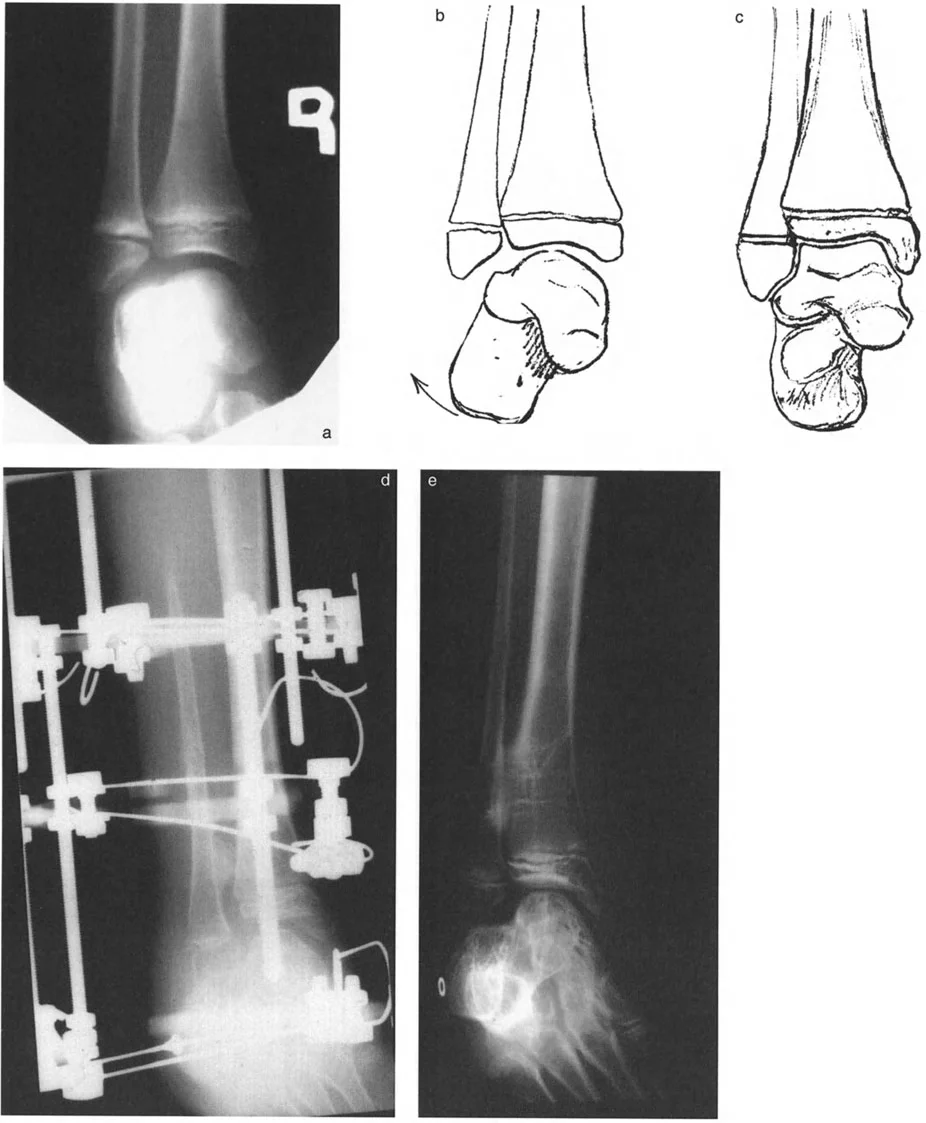

* نقص تنسج الشظية (Fibular Hemimelia): وهي حالة يولد فيها الطفل بشظية (عظم الساق الأصغر) أقصر من الطبيعي أو مفقودة جزئيًا. هذا يؤثر بشكل كبير على نمو قصبة الساق والكاحل، مما يؤدي إلى تشوهات شديدة في المحاذاة منذ الولادة. في هذه الحالات، يكون مركز دوران التشوه (CORA) عادةً عند مستوى المفصل نفسه.

* الكسور غير الملتئمة أو الملتئمة بشكل خاطئ: إذا لم يتم علاج كسر في الجزء السفلي من قصبة الساق أو الكاحل بشكل صحيح، أو إذا حدث التئام للعظم في وضع غير طبيعي، فقد يؤدي ذلك إلى تشوه دائم. على سبيل المثال، كسر في الكاحل يلتئم مع تقوس (Varus) أو روحبة (Valgus) في قصبة الساق يمكن أن يغير ميكانيكا الكاحل بشكل جذري.

تُعد مبادئ الدكتور درور بالي حجر الزاوية في جراحة تصحيح تشوهات العظام. تركز هذه المبادئ على تحديد "مركز دوران التشوه" (CORA - Center of Rotation of Angulation) بدقة. إن موقع CORA يحدد كيفية تأثير التشوه على المفاصل المجاورة ويوجّه الجراح في اختيار مكان قطع العظم (Osteotomy).

• فهم CORA:

• إذا كان CORA قريبًا من مفصل الكاحل، فإن التشوه يؤثر بشكل أساسي على محاذاة الكاحل.

أنواع جراحات قطع العظم فوق الكاحل (Supramalleolar Osteotomy)

جراحة قطع العظم فوق الكاحل (SMO) هي الإجراء الأكثر شيوعًا لتصحيح تشوهات قصبة الساق البعيدة. تتضمن هذه الجراحة قطعًا دقيقًا في عظم الساق (القصبة) فوق مفصل الكاحل مباشرة، ثم إعادة محاذاة العظم وتثبيته في الوضع الصحيح. هناك عدة أنواع من هذه الجراحة: